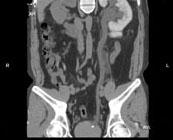

问题 男,29岁,反复发作血尿1年余,CT如图所示,下列说法正确的是 ( )

选项 A、左输尿管结石 B、膀胱结石 C、左侧输尿管扩张 D、左侧输尿管末端,膀胱入口处可见高密度影 E、左侧肾盂扩张积水

答案 ACDE